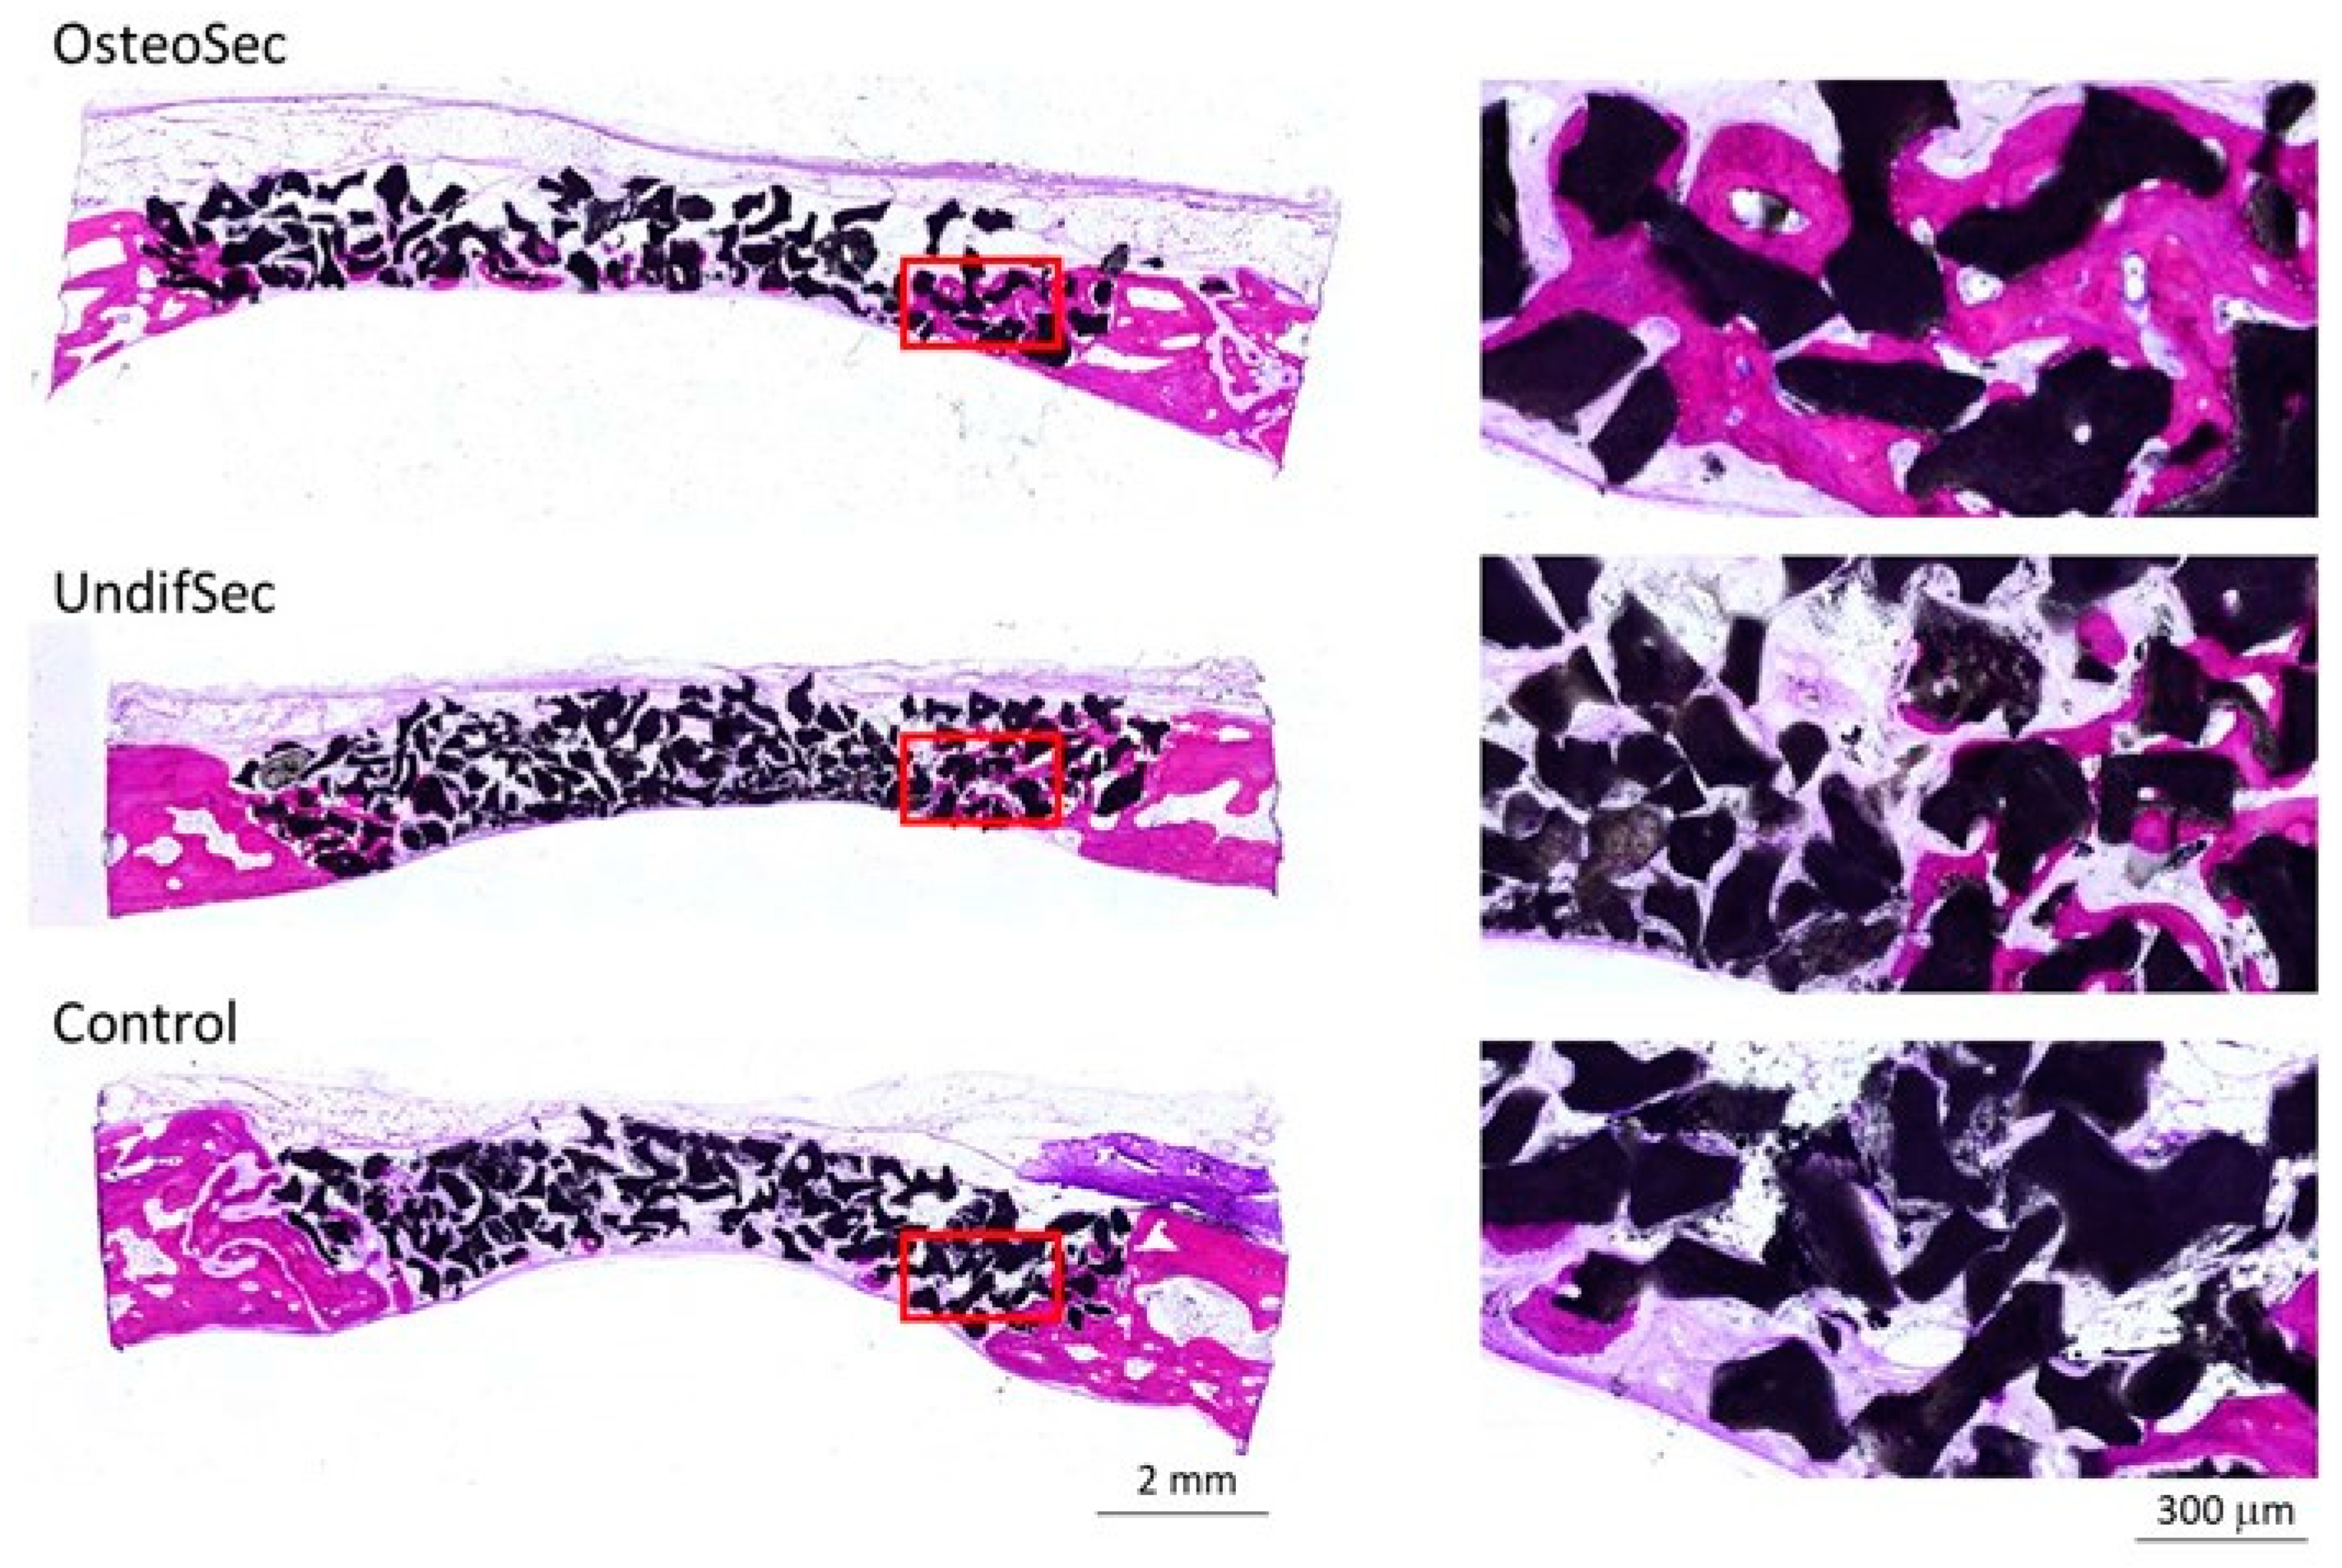

2.7.2. Histological and Histomorphometric Evaluation

3.2. The Bone Healing in Rabbit Calvarial Critical Size Defects

3.3. Secretome Modulation of the Bone Healing Process